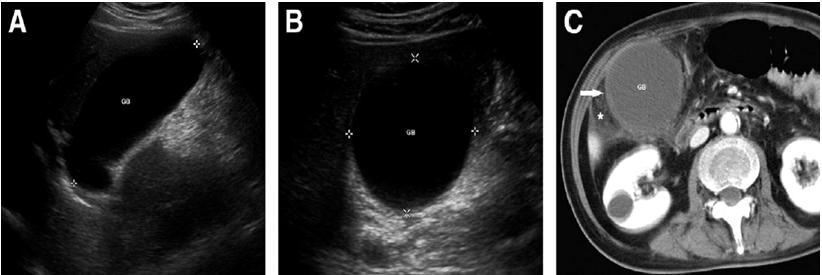

急性非结石性胆囊炎与急性结石性胆囊炎的临床表现大致相同,其诊断可基于腹部超声和CT检查中发现的胆囊壁水肿增厚(超过3.5-4 mm)和胆囊周围积液。

肝胆亚氨基二乙酸(HIDA)闪烁扫描有利于检测胆囊功能。胆汁排泌分数下降(≤35%)可能提示胆囊排空功能低下。